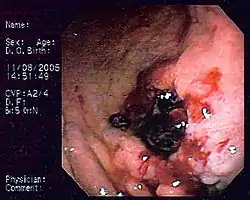

![]() صورة بالتنظير الداخلي للمفوما النسيج الليمفاوي المرتبط بالغشاء المخاطي (المخاطية) مأخوذ من جسم المعدة لدى مريض مصاب بنزيف الجهاز الهضمي العلوي. المظهر شبيه بقرحة المعدة مع خثرة ملتصقة. صورة بالتنظير الداخلي للمفوما النسيج الليمفاوي المرتبط بالغشاء المخاطي (المخاطية) مأخوذ من جسم المعدة لدى مريض مصاب بنزيف الجهاز الهضمي العلوي. المظهر شبيه بقرحة المعدة مع خثرة ملتصقة. | |